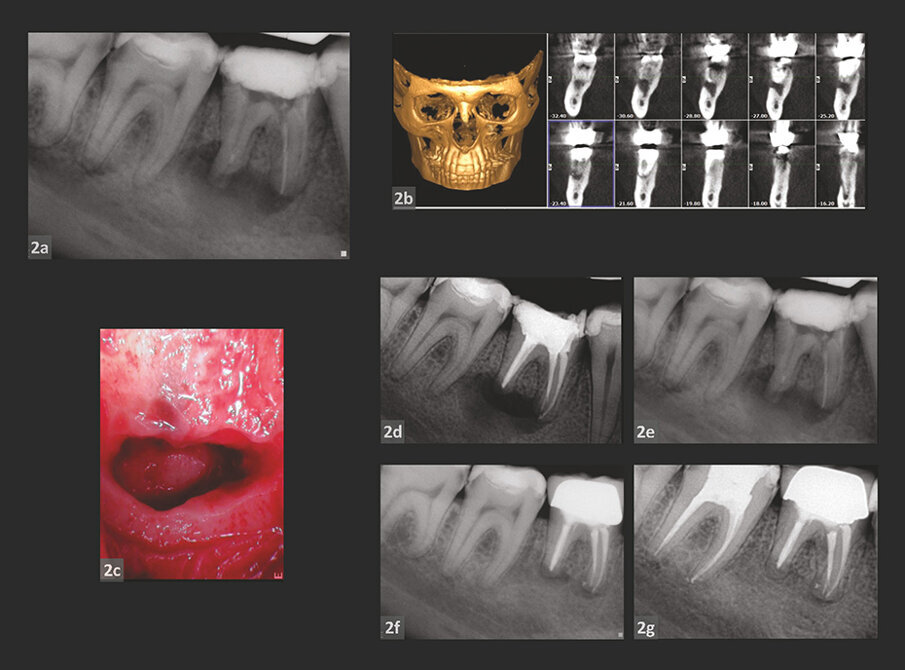

SLUČAJ 3

Slike 3a–3c: Preoperativni rendgenski snimci: gornji prednji zubi.

Slike 3d i 3e: CBCT skeniranje.

Slike 3f i 3g: Intraoperativne fotografije koje pokazuju nedostatke kosti kao rezultat cističnih reakcija.

Slike 3h–3j: Postoperativne radiografije neposredno nakon intervencije.

Slike 3k i 3l: Radiografije nakon18-mesečnog praćenja.

Pacijent muškog pola upućen je u kliniku na pregled status anjegovih gornjih prednjih zuba. Pacijent je dobio krune nekoliko godina ranije, a po svemu sudeći pulpa tih zuba je postala nekrotična, što je dovelo do periapikalne infekcije.

Na preoperativnim rendgenskim snimcima i na i-Cat skenu (slike 3a–e), periapikalne ciste mogu biti lako identifikovane zajedno sa masivnim gubitkom kosti.

Korišćen je pristup nulte apikotomije kako je opisano ranije u tekstu u cilju lečenja svih gornjih prednjih zuba i za uklanjanje višestrukih cista, uz očuvanje kosti i korena što je više moguće i samo je defekt kosti koji je nastao infekcijom iskorišćen za vađenje cisti (slike 3f i g).

Postoperativne radiografiski snimci (slike 3h–j) rađeni su odmah nakon intervencije, kao i tokom 18 meseci praćenja (slike 3k i l). Dalje praćenje nije bilo moguće jer je pacijent nakon toga bio nedostupan. Međutim, naknadni rendgenski snimci pokazuju smanjenje radiolucencije, što nam omogućava da pretpostavimo da je regeneracija kosti u procesu i da se formirao novi PDL.